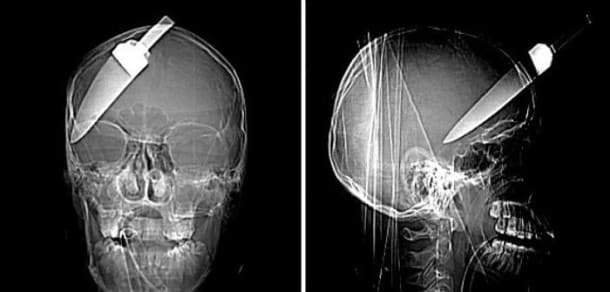

33 radiographies qui prouvent que les gens font des choses douteuses avec leur corps !